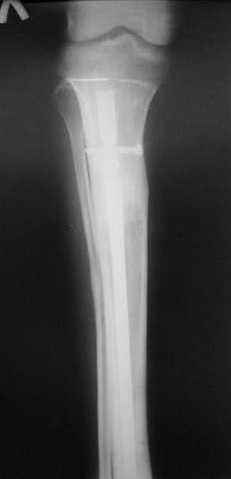

7, 8, 9, 10, 11 - через 8 мес после травмы перелом сросся.

Пациент ходит без дополнительной опоры, не хромает (видеоролик выложил сюда